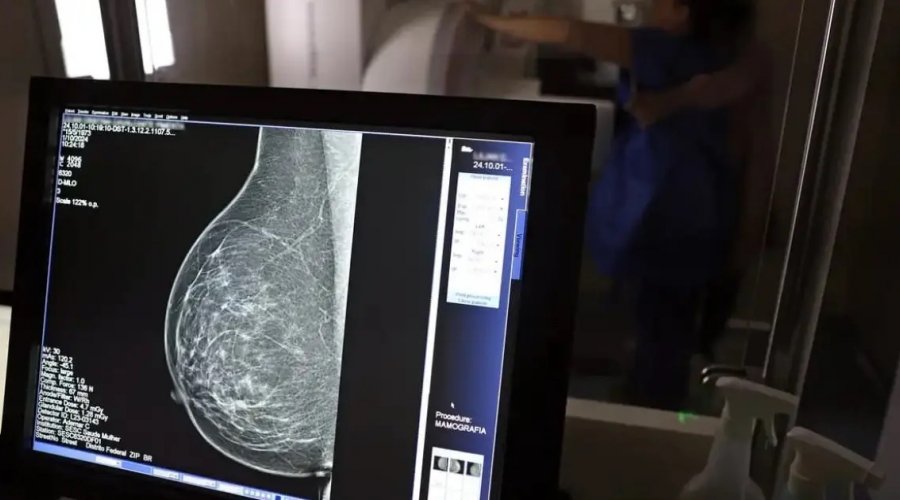

Foto: José Cruz / Agência Brasil

A Superintendência de Estudos Econômicos e Sociais da Bahia (SEI) divulgou o relatório Info Câncer de Mama 2025, que atualiza os dados sobre a doença no estado. O levantamento estima 4,3 mil novos casos em 2024 — uma taxa de 43,8 por 100 mil mulheres. Em Salvador, o número é ainda maior: 64,3 por 100 mil.

O câncer de mama segue como o tipo mais letal entre as mulheres baianas, representando 16% de todas as mortes por neoplasias malignas no estado, com 1,4 mil óbitos registrados em 2024. A taxa de mortalidade foi de 17,5 a cada 100 mil mulheres.

O relatório também aponta que a doença respondeu por cerca de 5 mil internações no SUS, com taxa de letalidade de 7 a cada mil. A campanha